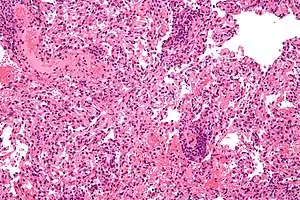

Micrograph showing lung transplant rejection. Lung biopsy. H&E stain.